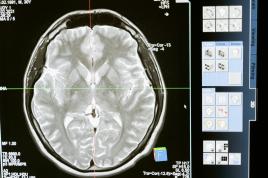

ÇEVİRİ Epilepsi nöbetlerini önceden fark eden "benzersiz" bir başlık geliştirildi Nicole Wootton-Cane